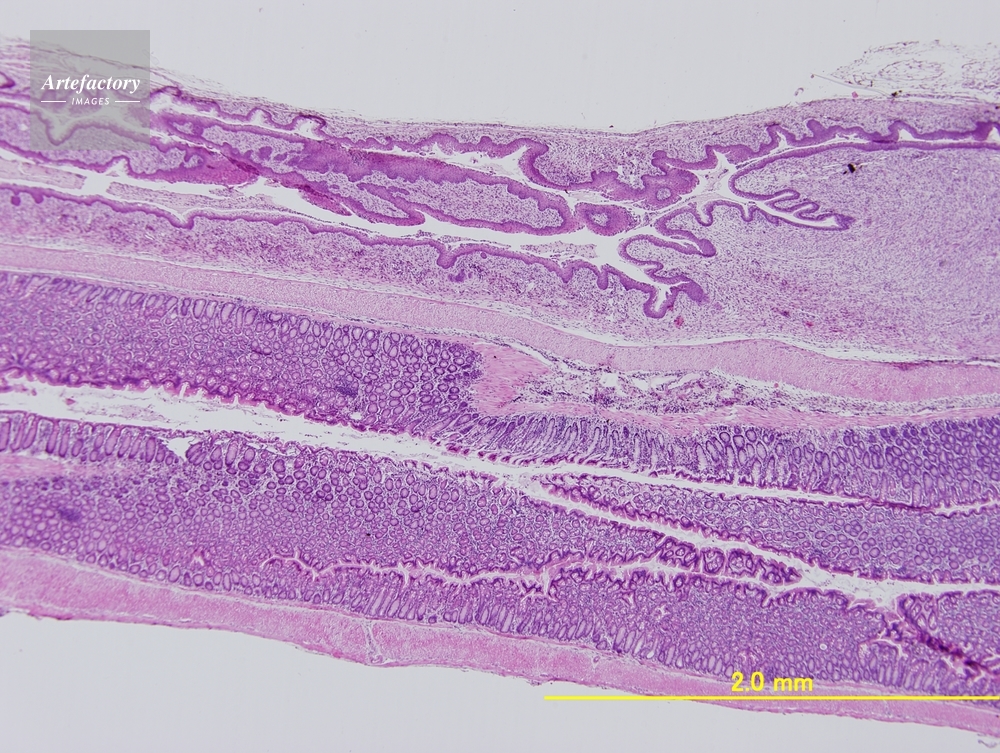

| 作品タイトル | マウス 膣、子宮、直腸 | モデルリリース | なし | |